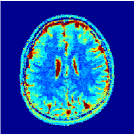

According to [44] as we progress into deeper layers, partitions will be subdivided into smaller segments in a hierarchal fashion. This can be observed in Figure 2 where we adopted the above routine for the T1/T2 encoding MRF sequence used in our experiments and visualised multi-scale (from coarse-to-fine) partitions obtained after each residual layer. The Bloch response manifold is sampled across fine-gridded T1/T2 values (i.e. MRF dictionary) to visualise the intersection of the input space segments with this manifold (results are visualised across the three dominant principal component axes). MRFResnet encoder learns about a thousand partitions for its end-to-end mapping . In the light of (16) we know that for each partition the network implicitly encodes deep matched-filters (the rows of or alternatively ) and an offset term to locally linearly regress the T1/T2 outputs in that segment. As such instead of memorising 100K dictionary atoms used for training, the network learns a compact piece-wise affine approximation to the Bloch manifold projection (5) as a rapid and memory-efficient alternative to DM’s point-wise approximation (7). The total number of parameters used by the MRFResnet (Table I) are two hundreds times less than the size of the dimension-reduced MRF dictionary. Figure 3 shows the Bloch responses for a range of T1/T2 values, as well as deep matched-filters learned by MRFResnet to predict each of these quantities in this range from noisy inputs. Computed through (17), match-filters are one-dimensional analogues of the saliency maps a.k.a. deep dream images [49], measuring sensitivities of the T1/T2 output neurons with respect to the inputs.